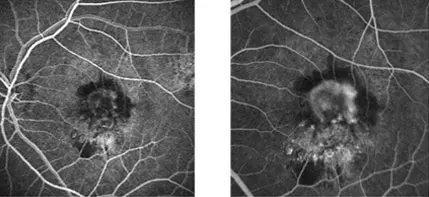

Otro estudio que en ocasiones se solicita es una angiografía digital con fluoresceína o retinofluoresceinografía (RFG). Para esta última prueba se inyecta un medio de contraste especial en una vena del brazo. Se toman fotografías cuando el contraste pasa por los vasos sanguíneos en la retina. Esta prueba le permite a su oculista detectar si tiene algún vaso sanguíneo anómalo y así puede recomendar algún tratamiento.

maculopatia